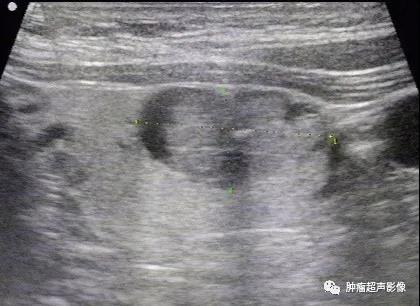

2、形态不规则:虽然甲状腺囊性乳头状癌的壁恶性肿瘤细胞分布较少,但是部分仍然按浸润性生长方式,导致形态不规则,而结甲囊性变一般呈光滑的圆形或椭圆形,因此形态不规则诊断甲状腺囊性乳头状癌具有高度的特异性。

多年体检诊断为结节囊性变,肿块整体形态不规则,内部实性部分形态也不规则,因此我考虑乳头状癌,术后病理证实为乳头状癌